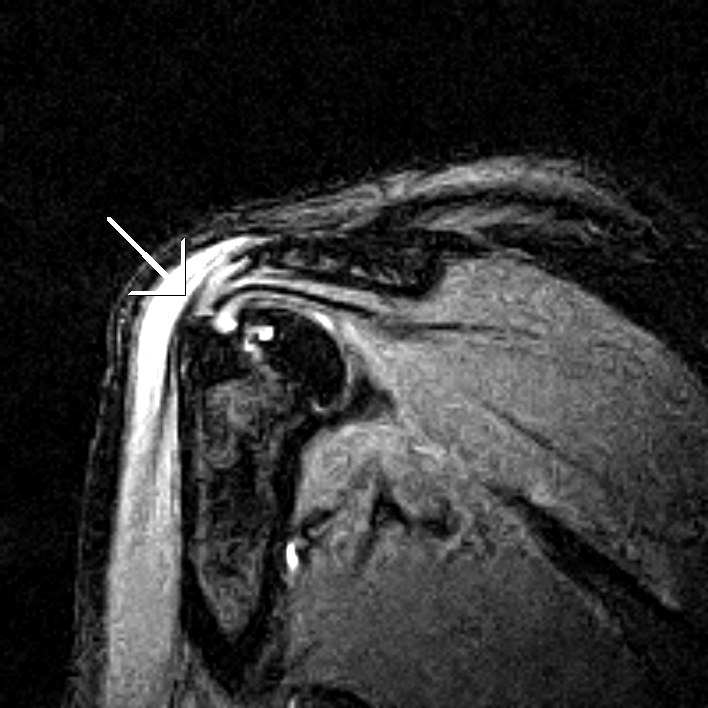

From sumerdoc.blogspot.com

Pitching InjuryMRI Shoulder Sumer's Radiology Blog Shoulder Injuries In Pitchers although throwing injuries in the shoulder most commonly occur in baseball pitchers, they can be seen in any athlete who participates in sports that require repetitive overhead. It is estimated that more than 57%. shoulder pathology can manifest as pain, diminished performance (velocity and accuracy), or a decrease in strength or range of motion. this review describes. Shoulder Injuries In Pitchers.

Pitching InjuryMRI Shoulder Sumer's Radiology Blog Shoulder Injuries In Pitchers this review describes a range of shoulder injuries experienced by baseball pitchers. shoulder pathology can manifest as pain, diminished performance (velocity and accuracy), or a decrease in strength or range of motion. little leaguer's shoulder is an overuse injury occuring in young baseball pitchers resulting in epiphysiolysis of the proximal humerus (a salter harris. It is estimated. Shoulder Injuries In Pitchers.